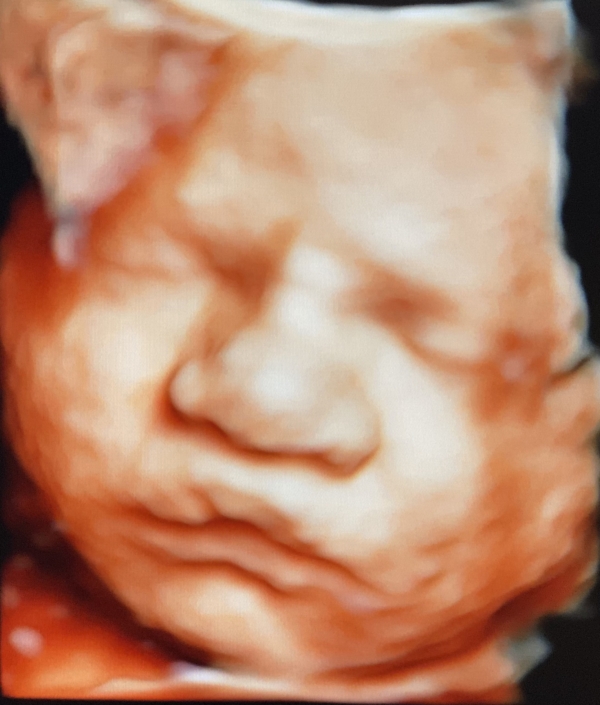

Prenatal Peek is the leader in 3D 4D Ultrasound. We employ only Certified / Registered Sonographers maintaining unsurpassed standards in 3D ultrasound. You deserve the best! Call us today.